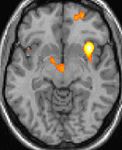

Positron emission tomography (PET) shows brain areas being activated during pain

Positron emission tomography (PET) scans indicate the brain areas which are activated during attack only, compared to pain free periods. These pictures show brain areas that are active during pain in yellow/orange color (called "pain matrix"). The area in the center (in all three views) is specifically activated during CH only. The bottom row voxel-based morphometry (VBM) shows structural brain differences between individuals with and without CH; only a portion of the hypothalamus is different.[33]